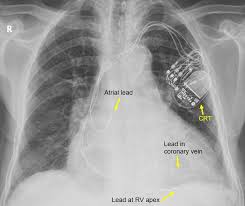

Pacemaker vs icd pacemakers icds ellenbogen, clin cardiac pacing 4th ed., p.776, 9 battery circuitry capacitor pacemaker icd implantable loop recorders jacob et al, heart rhythm vol 8 no 6 june 2011 cxr assessment • define the pulse generator location • confirm the device is a pacemaker There are 2 leads connected to the icd that course through the central veins in the chest to the heart. Fixed (asynchronous) pacing carries risk of r on t, however, there is little outcome data to support a preference for either. Later came the transvenous icd, which is implanted in the shoulder area. Icd therapy is a very trustworthy therapy that has prolonged hundreds of thousands of lives. If not identifiable, then proceed to step 4. All icds have a pacemaker function! Nice little tip from the emergency board review videos:

It works very much like a pacemaker. Implantable cardiac conduction devices (also known as cardiac implantable electronic devices or cieds) are a very common medical device of the thorax, with over one million implanted in the united states of america alone. Anesthesia professionals should know what type of device the patient has (pacemaker vs. There are 2 leads connected to the icd that course through the central veins in the chest to the heart. I have been competively swimming for 12 years. The purpose of this article is to review the normal and abnormal radiographic appearances of cardiac pacemaker and implantable cardioverter defibrillator systems. They are now what make the heart beat normally because our own muscles cannot do that anymore. Now there is a solution courtesy of the em rems blog: In 2009, more than 300,000 adults and children in the united states underwent placement of a new pacemaker or icd, and over 150,000 patients underwent revision .all u.s. Look for any sign of infection, ask for u/a, blood cx's, cxr if there is any question. If not identifiable, then proceed to step 4. Case discussion note the slightly larger control box of the implantable cardiac defibrillator when compared to a normal permanent pacemaker. Dual lead icd projects over the left chest.

Implantable cardiac conduction devices (also known as cardiac implantable electronic devices or cieds) are a very common medical device of the thorax, with over one million implanted in the united states of america alone. It works very much like a pacemaker. Pacemakers have a more regular function; The first day i swam in the 800 meter freestye. The less invasive subcutaneous (under the skin) icd. All icds have a pacemaker function but not all pacemakers are icds. I dread calling cardiology to interrogate a pacemaker when the pt is without their wallet card and has nary a clue as to the device type/manufacturer. Cardiac pacemaker and implantable cardioverter defibrillator (icd) systems are commonly seen on chest radiographs. An implantable cardioverter defibrillator (icd) looks similar to a pacemaker, though slightly larger. The pacemaker device keeps the heart from beating too slowly. When icd devices were first introduced in the 1980s, they were implanted in the abdomen. The purpose of this article is to review the normal and abnormal radiographic appearances of cardiac pacemaker and implantable cardioverter defibrillator systems. A biventricular pacemaker and icd help keep the heart pumping in a more normal way.

Chest radiographs showing pacemakers and implantable cardioverter defibrillators contain identifying and clinically relevant information, such as mri compatibility and. Difference between icd and pacemaker while both the icd and pacemaker deal with matters of the heart, they have different functions. Case discussion note the slightly larger control box of the implantable cardiac defibrillator when compared to a normal permanent pacemaker. Nice little tip from the emergency board review videos: In 2009, more than 300,000 adults and children in the united states underwent placement of a new pacemaker or icd, and over 150,000 patients underwent revision .all u.s.

This step is crucial for determining the type of the device implanted: There are two major types of cardiac conduction devices: The less invasive subcutaneous (under the skin) icd. It tries to restore the normal squeezing pattern of the heart. Pacemaker vs icd pacemakers icds ellenbogen, clin cardiac pacing 4th ed., p.776, 9 battery circuitry capacitor pacemaker icd implantable loop recorders jacob et al, heart rhythm vol 8 no 6 june 2011 cxr assessment • define the pulse generator location • confirm the device is a pacemaker The first day i swam in the 800 meter freestye. All icds have a pacemaker function! Cardiac pacemaker and implantable cardioverter defibrillator (icd) systems are commonly seen on chest radiographs.